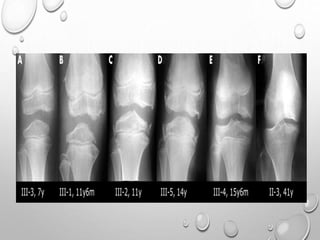

EPIPHYSEAL DYSPLASIA

MULTIPLEX

AD TRANSMISSION

EQUAL IN MALES AND FEMALES

FIRST NOTICED WHEN CHILD BEGINS TO WALK , WITH COMMON

COMPLAINTS OF WADDLING GAIT , DIFFICULTY RUNNING.

MILDER CASES MAY NOT APPARENT UNTIL EARLY ADULTHOOD ,

WHEN PREMATURE JOINT DEGENERATIVE CHANGES OCCURS.

PATHOPHYSIOLOGY : ABNORMALITY OF EPIPHYSEAL

CHONDROCYTES ( NO DECREASED , ABNORMAL ARRANGEMENT

)….LEADING TO DELAYED AND DISORDERLY OSSIFICATION F

EPIPHYSES.

LL >> UL

SHORT STATURE WITH TENDENCY TOWARDS DWARFISM

BILATERAL SYMMETRICAL INVOLVEMENT

DEVELOPMENT OF EPIPHYSES DELAYED

APPEARANCE IS MOTTLED WITH IRREGULAR MINERALIZATION

FLATTENED AND SQUARED-OFF EPIPHYSES

DOUBLE LAYERED PATELLA……PATHOGNMONIC

HYPOPLASTIC TIBIAL AND FEMORAL CONDYLES WITH SHALLOW

INTERCONDYLAR NOTCH

METAPHYSES ARE FLARED

CARPALS , TARSALS AND LONG TUBULAR BONES OF HAND ,SOMETIMES

FEET ARE SHORT AND THICK

SPINE : ANTERIOR WEDGING , SCOLIOSIS

IRREGULAR EPIPHYSES LEADS TO PREMATURE AND SEVERE

DEGENERATIVE CHANGE ESPECIALLY IN KNEES AND HIPS.